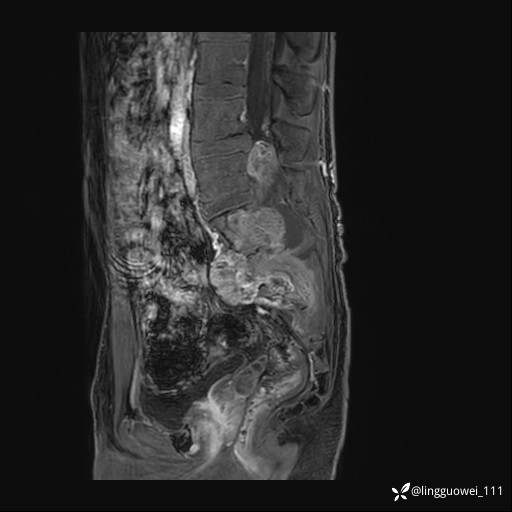

男,25岁,腰痛4年,加重左下肢痛5天,先上传X光片,第2天再上传CT。MR

MR:(忘记截图常规序列,不过应该不影响诊断)